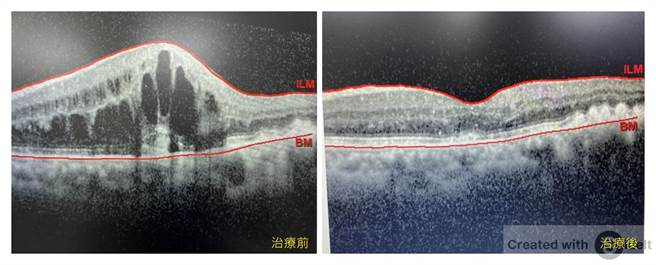

长安医院日前受邀到社区活动中心举办健康讲座,其中一场「医师教你顾目睭」活动,一名独居70岁陈先生到场听讲,当场向主讲医师:长安医院眼科医师彭书昱询问自己眼疾,经安排到院就医,检查后竟发现陈先生的左眼罹患眼中风,并造成黄斑部严重水肿,幸好,透过注射眼球内药物治疗,黄斑部消肿了,视力也进步很多。

彭书昱表示,如同脑中风是脑血管阻塞,眼中风就是视网膜血管发生阻塞,通常发病前毫无症状,发生时则急性、无痛性的视力模糊或视野缺损,严重者可能会造成失明,如同不定时炸弹。眼中风其实并不少见,其发生率仅次于糖尿病视网膜病变,一般好发年龄为50岁以上中老年人,尤其是患有青光眼、高血压、高血脂、糖尿病的人及嗜饮酒、抽菸的人更要特别注意。

彭书昱提醒,如果发生急性、无痛性的视力模糊,应立即就医接受眼科医师的检查,以便及早获得适当的治疗。然而,一旦发生眼中风,视力往往会受到不可逆的损害。因此,最重要的是消除危险因子,并定期进行眼科检查,才能好好保护灵魂之窗。